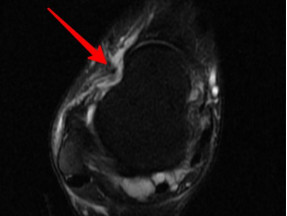

韌帶斷裂

幾經(jīng)輾轉(zhuǎn),李先生來到廣安醫(yī)院就診,骨科中心主任羅軍副主任中醫(yī)師為他進(jìn)行了詳細(xì)專業(yè)的查體,結(jié)合影像檢查,診斷為右踝關(guān)節(jié)不穩(wěn)(距腓前及跟腓韌帶斷裂)、右踝關(guān)節(jié)創(chuàng)傷性關(guān)節(jié)炎。羅軍主任帶領(lǐng)大家詳細(xì)分析病情之后,決定為他施行踝關(guān)節(jié)鏡下病變組織清理和距腓前韌帶、跟腓韌帶重建術(shù)。

醫(yī)生們?cè)谑中g(shù)中發(fā)現(xiàn),李先生的右踝關(guān)節(jié)軟骨損傷明顯,踝關(guān)節(jié)前方及內(nèi)外側(cè)均有不同程度的骨質(zhì)增生,相互撞擊引起疼痛,同時(shí)距腓前及跟腓韌帶斷裂。手術(shù)醫(yī)生利用磨鉆,小心翼翼將引起撞擊的骨刺一一去除,然后,修復(fù)了損傷的關(guān)節(jié)軟骨,最后,為他完成了距腓前和跟腓韌帶的修復(fù)。